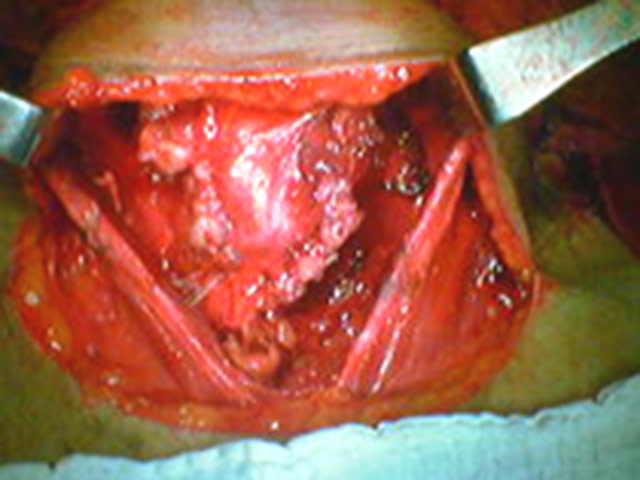

Bócio Colóide

Grande Bócio Tireoideano.

Exteriorização dos Lobos Tireoideanos.